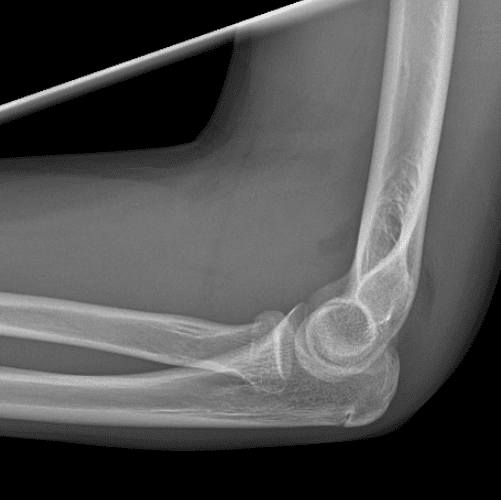

Simulates call by including subtle or difficult cases and some normals.

40 cases